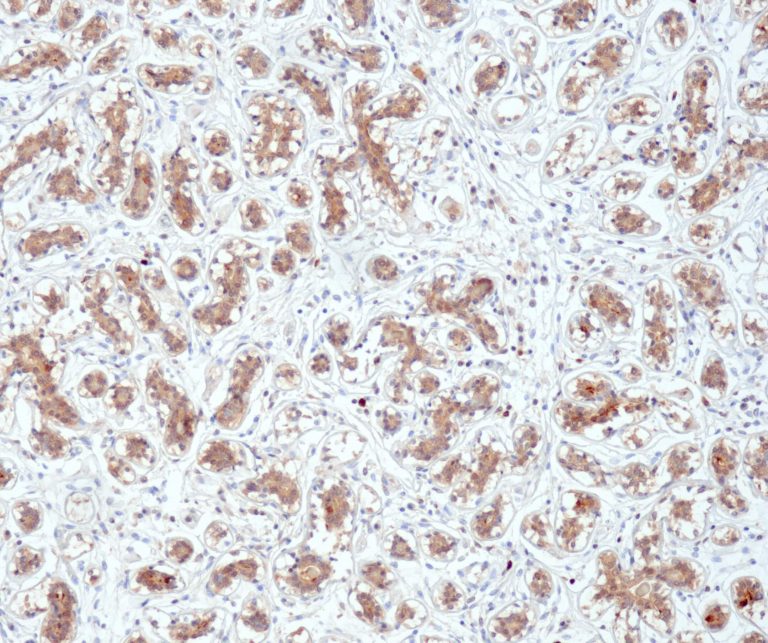

Vascular Pathology

Gastrointestinal (GI) Pathology

General Marker

Breast Pathology

Endocrine Pathology

Gynecological Pathology

Neuropathology

Infection Markers

Lung Pathology

Urinary Tract Pathology

Transplantation Pathology

Soft Tissue Pathology

Hematopathology